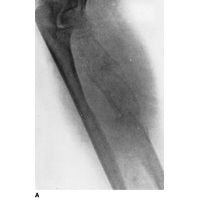

Plain film x-rays show a moth eaten lesion in the diaphysis. Lytic lesions are more common than blastic lesions and "onion skinning" may be present for sub-periosteal lesions.